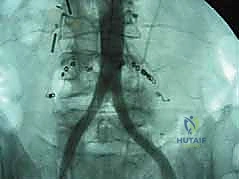

- الأشعة السينية الديناميكية (Dynamic X-rays): صور في وضعيات الانحناء للأمام والخلف لتقييم مدى عدم استقرار العمود الفقري (الانزلاق الفقري - Spondylolisthesis).

هذه هي الخطوة الأكثر دقة. أمام العمود الفقري القطني توجد الأوعية الدموية الكبرى في الجسم (الشريان الأورطي والوريد الأجوف السفلي وتفرعاتهما). باستخدام أدوات دقيقة ورؤية مكبرة، يتم تحريك هذه الأوعية بلطف شديد لحمايتها وكشف القرص الفقري المستهدف (غالباً L4-L5 أو L5-S1).